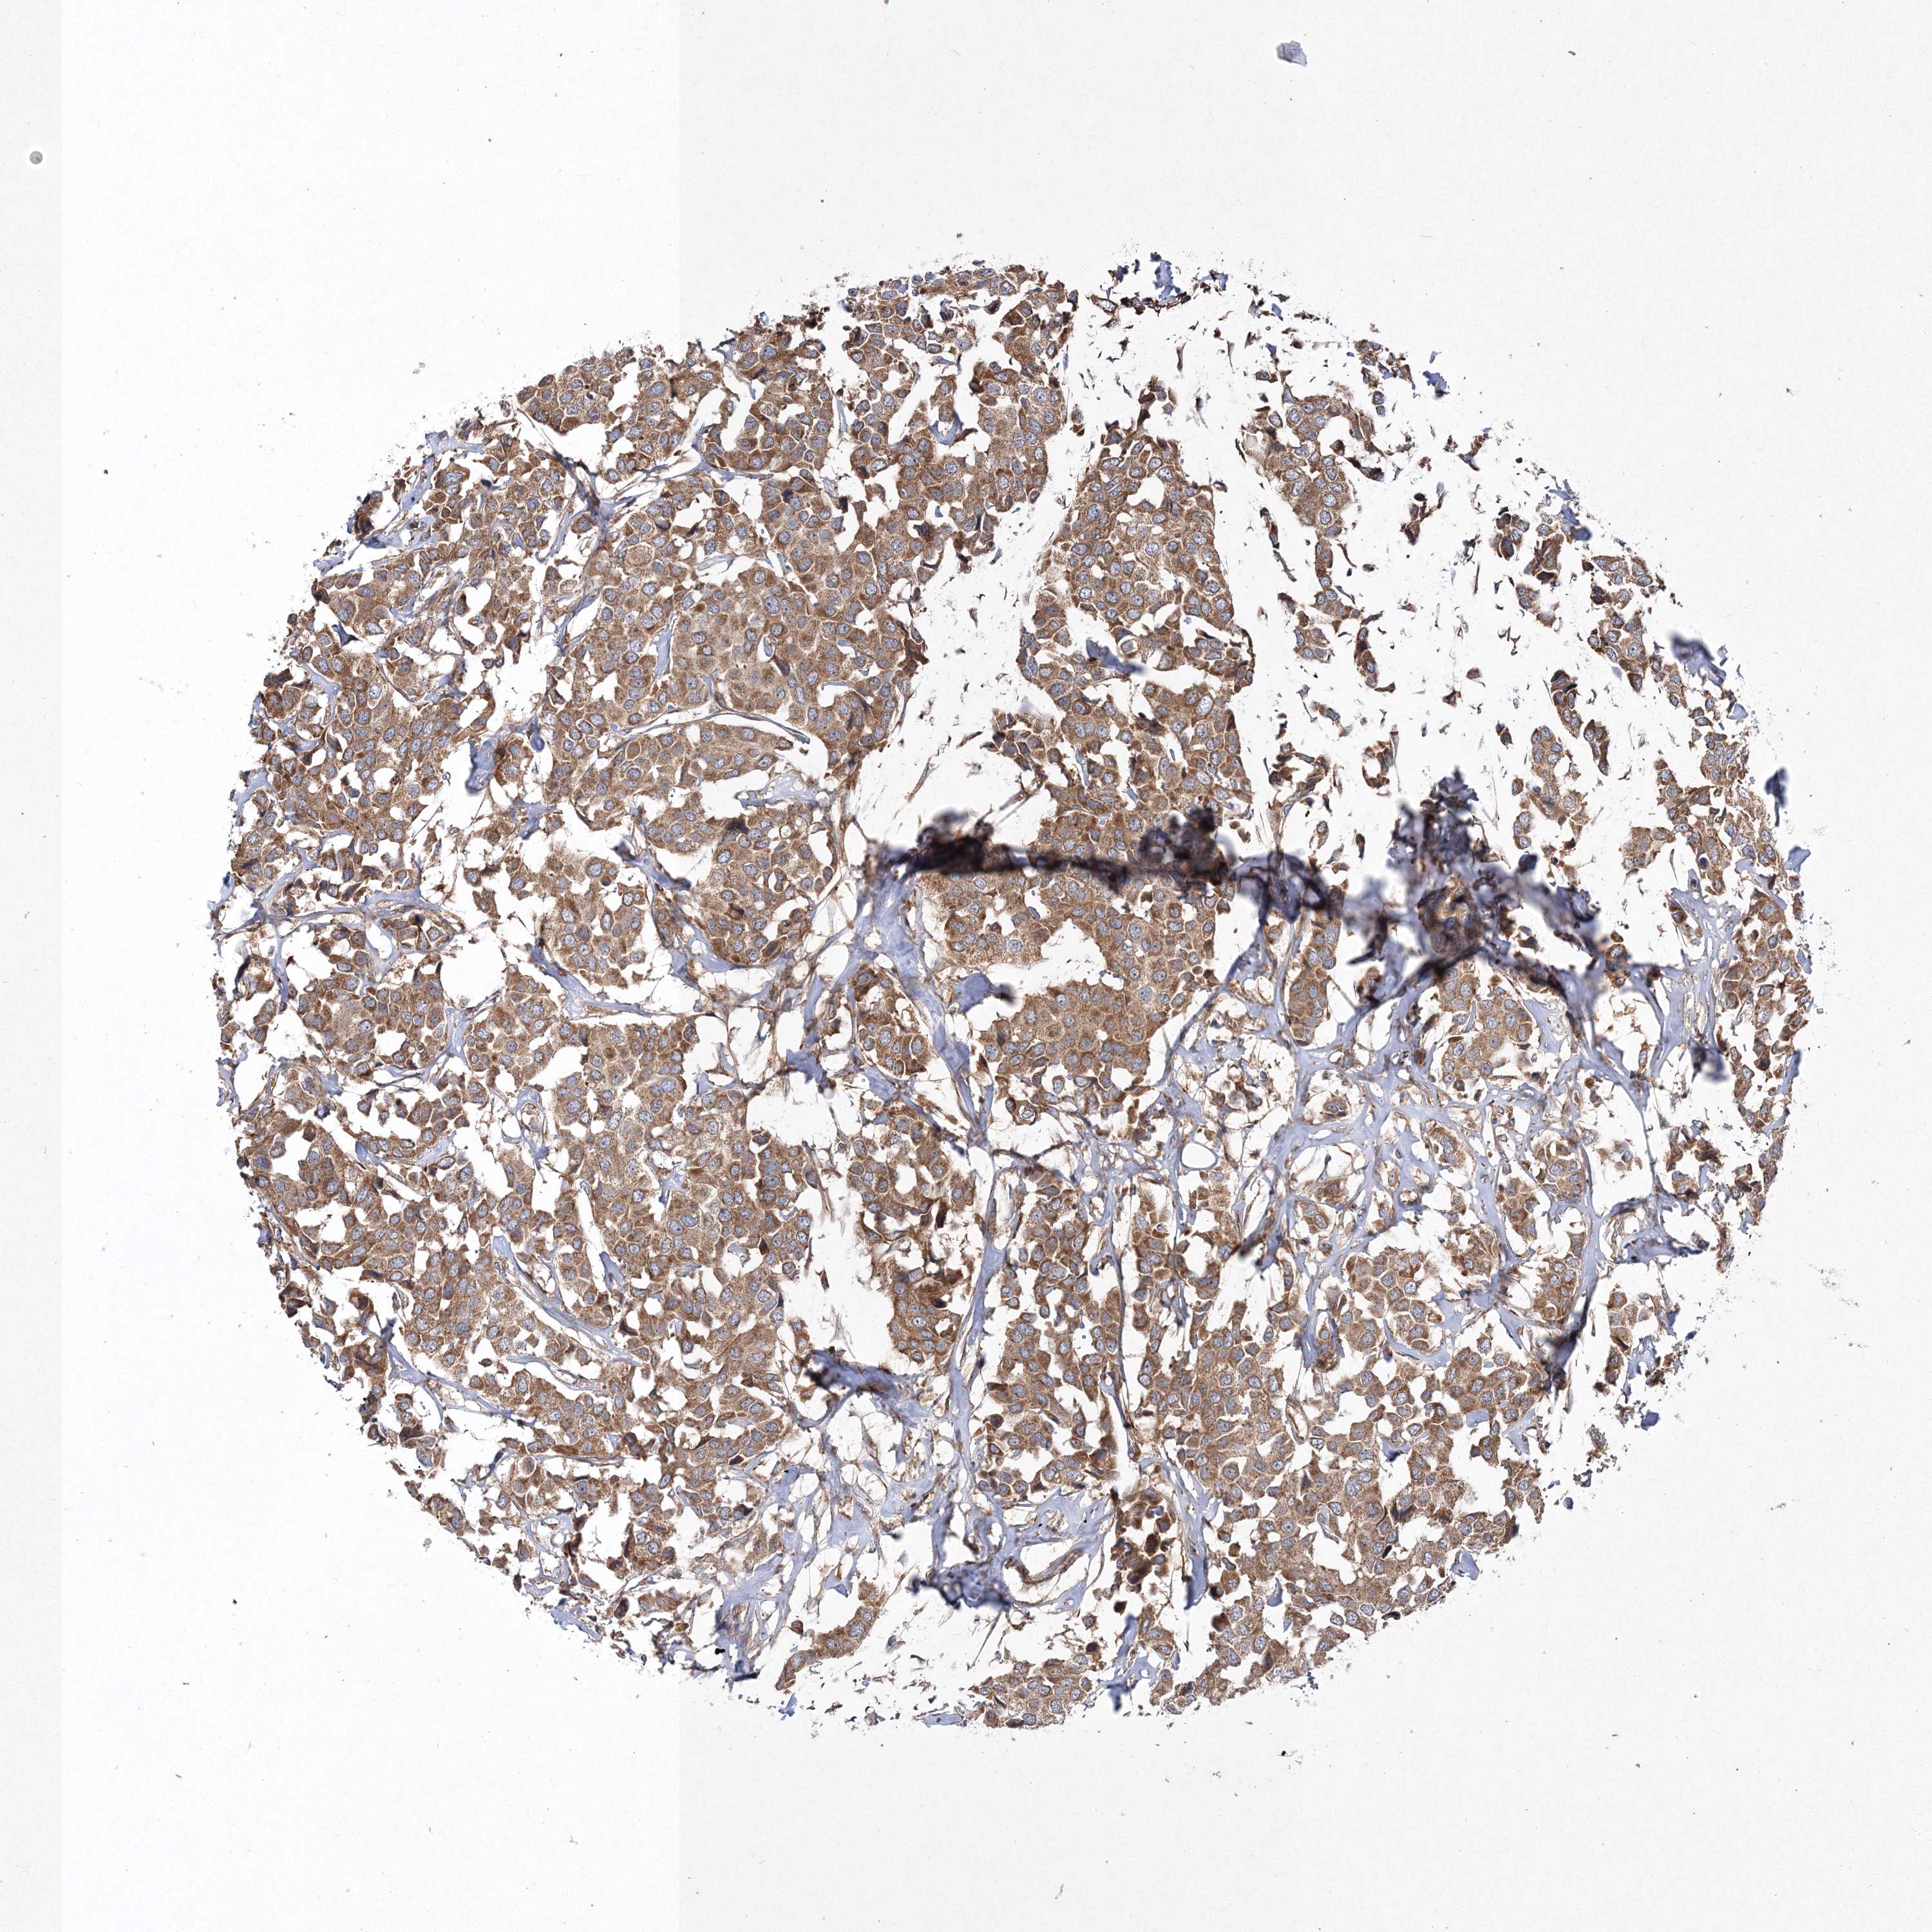

CANCER BREAST CANCER Show tissue menu

BRCA TCGA BRCA VALIDATION PROTEIN EXPRESSION